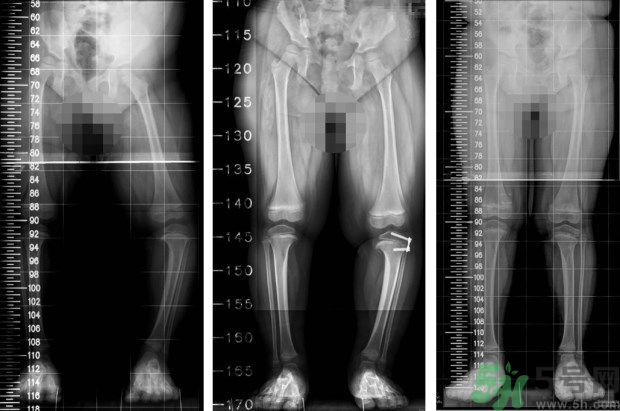

左圖:矯正前,4歲女童,左小腿外側(cè)的生長板過度發(fā)育,導(dǎo)致左腳O型腿;中圖:矯正中,在左小腿外側(cè)的生長板,夾上小夾子,矯正過度發(fā)育的生長板;右圖:矯正後,經(jīng)過1年的生長板導(dǎo)引治療,恢復(fù)正常的外觀。(照片提供:王廷明 醫(yī)師)